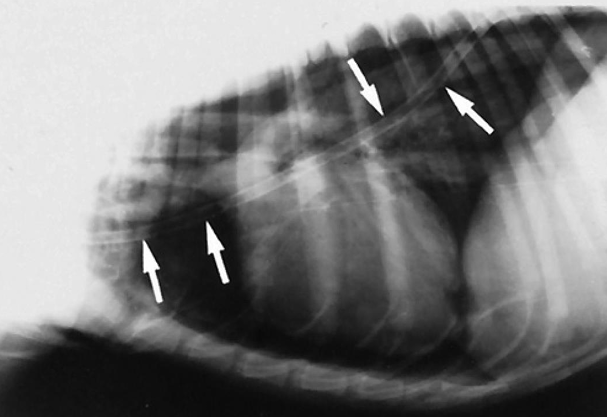

![]() | Mediastinum - abnormal shift - 여기서는 심장이 오른쪽으로 붙음 - 무기폐, 폐자름술, 폐종양일 때 발생 |

![]() | - 옆으로 몇 분 누워있었더니 무기폐 생긴 환자. - 무기폐가 생겨 심장이 왼쪽/오른쪽으로 틀어질 수 있음. - 섣불리 좌심비대로 평가하면 X |